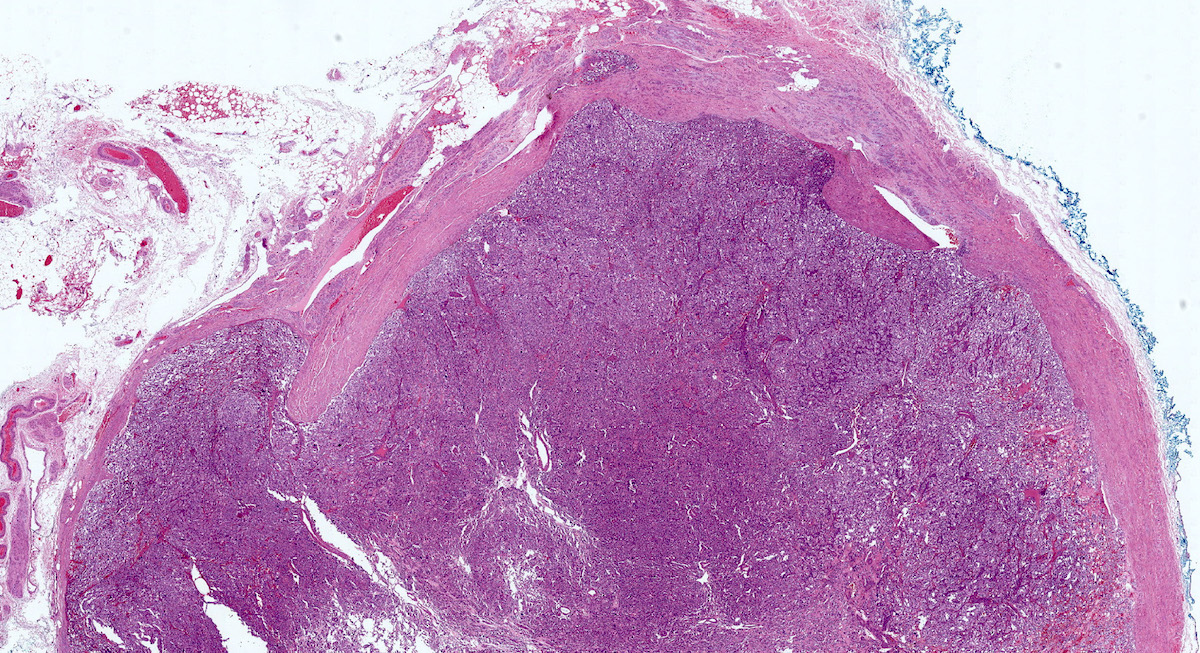

Microscopic (histologic) description

- Prevailing histologic pattern: epithelioid chief cells arranged in distinctive clusters / nests (zellballen pattern), separated by prominent fibrovascular stroma (J Clin Med 2018;7:280)

- Trabecular pattern: ribbons or cords of epithelioid cells divided by fibrous bands

- Other patterns: pseudorosette, angioma-like, spindled and sclerosing

- Chief cells: round, oval to polygonal cells with abundant granular basophilic, eosinophilic or amphophilic cytoplasm (Surg Pathol Clin 2019;12:951)

- Intracytoplasmic hyaline globules may be present in sympathoadrenal paragangliomas

- Giant multinucleated cells and bizarre cells can be present (Srp Arh Celok Lek 2002;130:7)

- Rarely, elongated and spindle shaped cells with a sarcomatoid appearance may be found

- Scattered ganglion cells can be seen

- May have nuclear atypia

- May have dysmorphic vessels, melanin-like pigment (neuromelanin) (pigmented paraganglioma), amyloid, abundant stroma and osseous metaplasia (Diagn Pathol 2012;7:77, Hum Pathol 1992;23:33)

- No or rare mitotic figures except in highly aggressive rapidly proliferating lesions

- May have focal chronic inflammatory infiltrate

- Necrosis is unusual except in patients who have undergone preoperative tumor embolization

- Special histopathologic features usually related to genetic syndromes:

- VHL syndrome: prominent stromal edema, clear cytoplasm and lipid degeneration (Am J Surg Pathol 1987;11:480)

- SDHx related syndrome: granular eosinophilic cytoplasm (Am J Surg Pathol 2020;44:422)

- MEN2 syndrome: unilateral or bilateral adrenal medullary hyperplasia (Neoplasia 2014;16:868)

Microscopic (histologic) images

Contributed by Luvy Delfin, M.D. and Sylvia L. Asa, M.D., Ph.D.